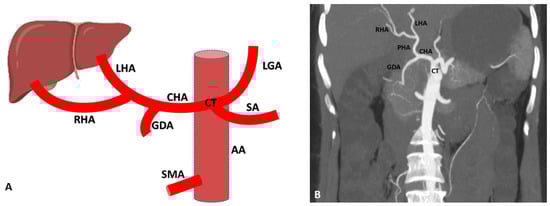

3.1. Variations of Common Hepatic Artery

3.2. Variations of Right Hepatic Artery

3.3. Variations of Left Hepatic Artery

4. Detection of Hepatic Artery Variations and Their Classifications